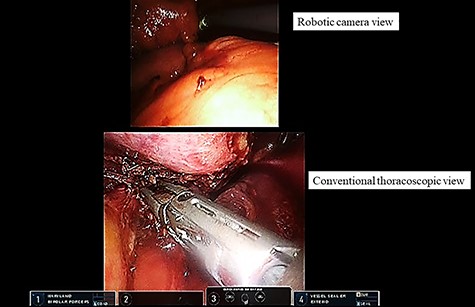

During robotic surgery, we divided the pericardium to gain an adequate surgical margin. However, the tumor itself was too large to observe the cranial and dorsal sides of the tumor as well as the intrapericardial space. We used conventional thoracoscopy to overcome this limitation. The thoracoscopic image was shown in the TilePro multi-display (Fig. 3). With the aid of both the robotic camera and conventional thoracoscope, the surgeon safely achieved complete resection of the tumor (Fig. 3). The tumor was retrieved via a subxiphoid incision. Finally, we performed pericardial reconstruction under robotic surgery.

Dual-scopic approach. With the aid of a dual-scopic approach using both a robotic camera and conventional thoracoscopic images, minimally invasive surgical resection of a challenging thymic tumor was achieved.